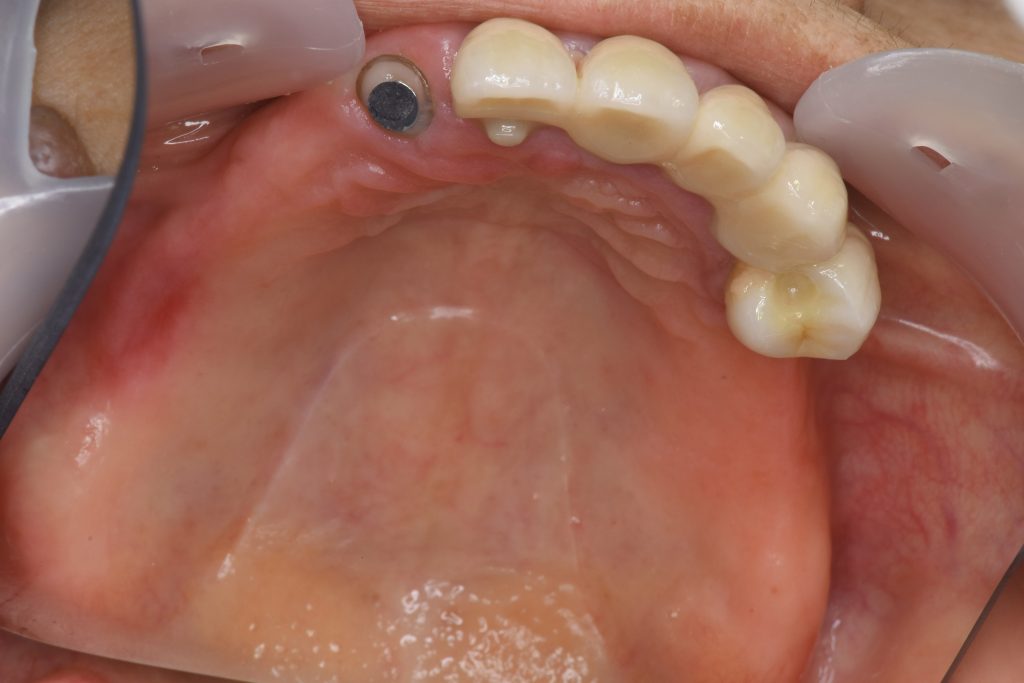

症例1メタルプレート

60代 女性 主訴 前歯部審美障害、義歯が揺れて噛めない。

前歯部はジルコニアにて修復後、三次元構成義歯を作製(残存歯と義歯の一体化を図る)

費用 205万(仮義歯・メタルプレート・マグネット・金属歯まで含む)